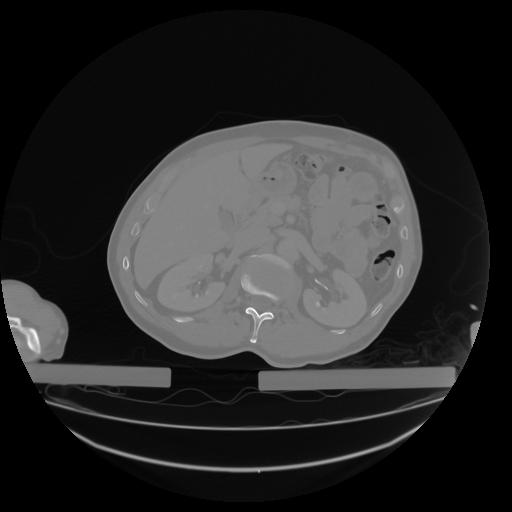

27 CUERPO,CE,Axial,3.0,CUERPO,,